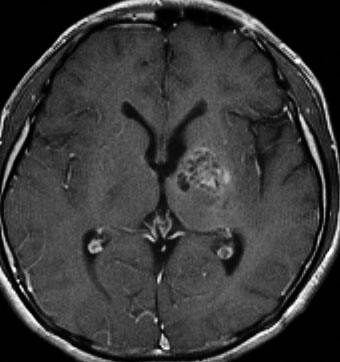

ICE化学療法投与開始から数日で小さくなります

この例は古いので第3脳室開窓術 ETV をしていません。左はICE化学療法前。中央は9日後。右は25日後です。閉塞性水頭症があっても1週間くらいで中脳水道が通って水頭症は改善します。ジャーミノーマであれば,ICE化学療法1コースでかなり縮小するはずです。このような顕著な効果がない時には,逆にジャーミノーマ以外の胚細胞腫瘍が混在していると考えた方がいいでしょう。多くは奇形腫の混在です。